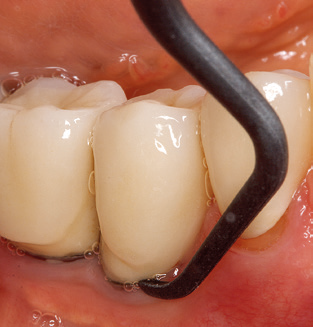

Die gute Ausleuchtung des Arbeitsfeldes stellt eine wesentliche Erleichterung dar. Bei dem von den Autoren genutzten System ist dies gelungen, indem ein 5facher LEDRing in das Handstück integriert wurde. Natürlich werden für dieses System unterschiedliche Arbeitsspitzen für die jeweiligen Indikationsbereiche angeboten. Eine gerade, universell einsetzbare Spitze ist das Basisinstrument zur maschinellen Instrumentierung natürlicher Zähne (Abb. 5a und b). Für schwer zugängliche Bereiche im Seitenzahnbereich werden gebogene Spitzen angeboten, die auch einen Zugang zu freiliegenden Furkationen ermöglichen (Abb. 6).

Nach der maschinellen Reinigung der Zahn und Implantatoberflächen erfolgt eine manuelle Instrumentierung der natürlichen Zahnoberflächen mit konventionellen Handinstrumenten. Bei der manuellen Reinigung ist insbesondere auf einen korrekten Anstellwinkel, eine ausreichende Schärfe, eine gute Abstützung und auf eine von apikal nach koronal gerichtete Arbeitsweise der Kürette zu achten. Zur Nachinstrumentierung der Implantatkonstruktionen sollten entweder Titan oder Carbonküretten verwendet werden (Abb. 8). Ergänzend zum Einsatz von Ultraschallgeräten können in der Erhaltungstherapie auch Pulverstrahlgeräte genutzt werden. Dabei ist jedoch zu berücksichtigen, dass diese Verfahren nicht zum Entfernen harter Beläge geeignet sind und daher die Verwendung von Hand oder Ultraschallinstrumenten nicht komplett ersetzen können. Abschließend erfolgt in jedem Fall eine mechanische Politur der zugänglichen Zahn und Implantatoberflächen mit Polierkelchen und Polierpasten (Abb. 9).